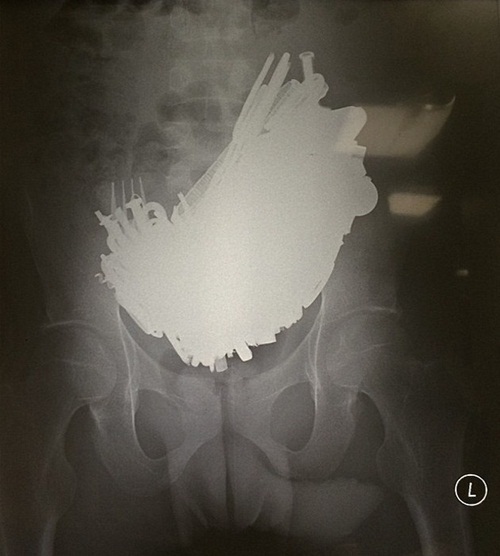

นายแพทย์ไนดู แพทย์เจ้าของไข้เผยว่า ตอนแรกคิดว่าผู้ป่วยน่าจะมีแผลในทางเดินอาหาร เพราะอาเจียนเป็นเลือด แต่ภาพเอกซเรย์กลับทำให้ช็อกหนัก เมื่อเห็นวัตถุแปลกปลอมที่น่าจะเป็นโลหะอัดแน่นเต็มกระเพาะของผู้ป่วยไปหมด หนำซ้ำยังรั้งกระเพาะที่ให้หย่อนลงมาอยู่ที่ท้องช่วงล่างด้วย

การผ่าตัดเกิดขึ้นอย่างเร่งด่วน แพทย์ทำการกรีดเปิดหน้าท้องตั้งแต่ช่วงอกลงไปถึงสะดือ แล้วเปิดกระเพาะอาหาร คีบเอาวัตถุแปลกปลอมเหล่านั้นออกมาทีละชิ้น นับจำนวนได้ถึง 227 ชิ้น มีทั้งนอต ตะปู ลูกกุญแจ กลอนประตู ส้อม โซ่ ลวด แม้กระทั่งไขควง ทั้งหมดอยู่ในสภาพขึ้นสนิมจากการถูกน้ำย่อยในกระเพาะกัดกร่อน และชั่งน้ำหนักรวมกันได้ถึง 2 กิโลกรัม จึงไม่น่าแปลกใจว่าทำไมกระเพาะอาหารจึงได้หย่อนลงผิดตำแหน่ง